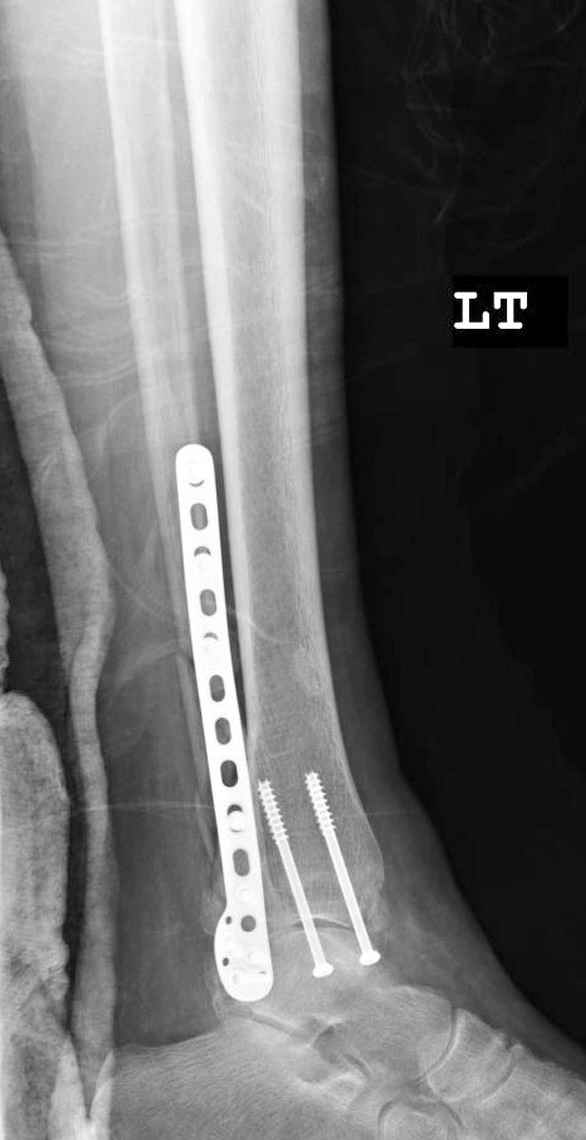

Пока я был в интернатуре, предпочитали осуществлять стабильный остеосинтез с ранней функцией. См. приложения и полнотекстный вариант

статьи.

В местных условиях практически все переломы лодыжек( нестабильные) оперируются открыто: 3.5 мм 1/3 пластина и спонгиозный винт со спицей или

два 4.5 мм спонгиозных винта. Почему я задаю вопрос, потому что во всех оперирируемых случаях наблюдал надкостничную интерпозицию в зоне перелома внутренней лодыжки, которая устраняется в процессе репозиции. Естественно, что при закрытой технике устранить интерпозицию евозможно/возможно? или сохраняющаяся межфрагментарная интерпозиция не кртитична для сращения перелома? Как вы прокомментируете это?